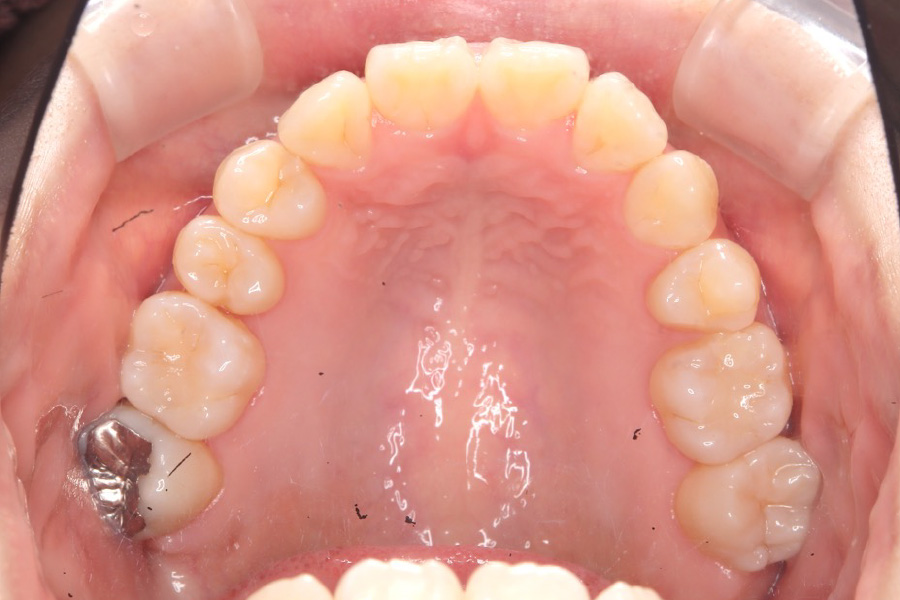

治療後

主訴 全体のガタつきが気になる

期間 2年

費用 220,000円〜660,000円

治療内容 インザライン矯正

小臼歯抜歯

治療に伴うリスク 矯正終了後は、リテーナーを指示通りに使用し、歯の後戻りを防ぐ必要があります。